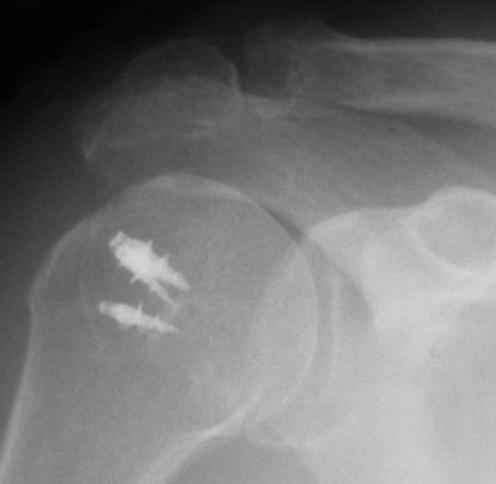

Верхний подвывих в такой ситуации может быть проявлением ротаторной артропатии, как следствия более массивного, чем частичный разрыв сухожилия надостной мыщцы, повреждения  вращательной манжеты. И значит нужно думать о том, насколько полно восстановлена манжета, адекватно ли был расценен объем ее повреждения. Что за шов применялся? Якорных винтов не видно. И почему гипсовая иммобилизация? Есть прекрасные надувные отводящие подушки, позволяющие ранние движения.

В качестве примера - снимки до и после восстановления целостности вращательной манжеты  после 3-хмесячной давности полного разрыва. Видно, что верхний подвывих устранен.